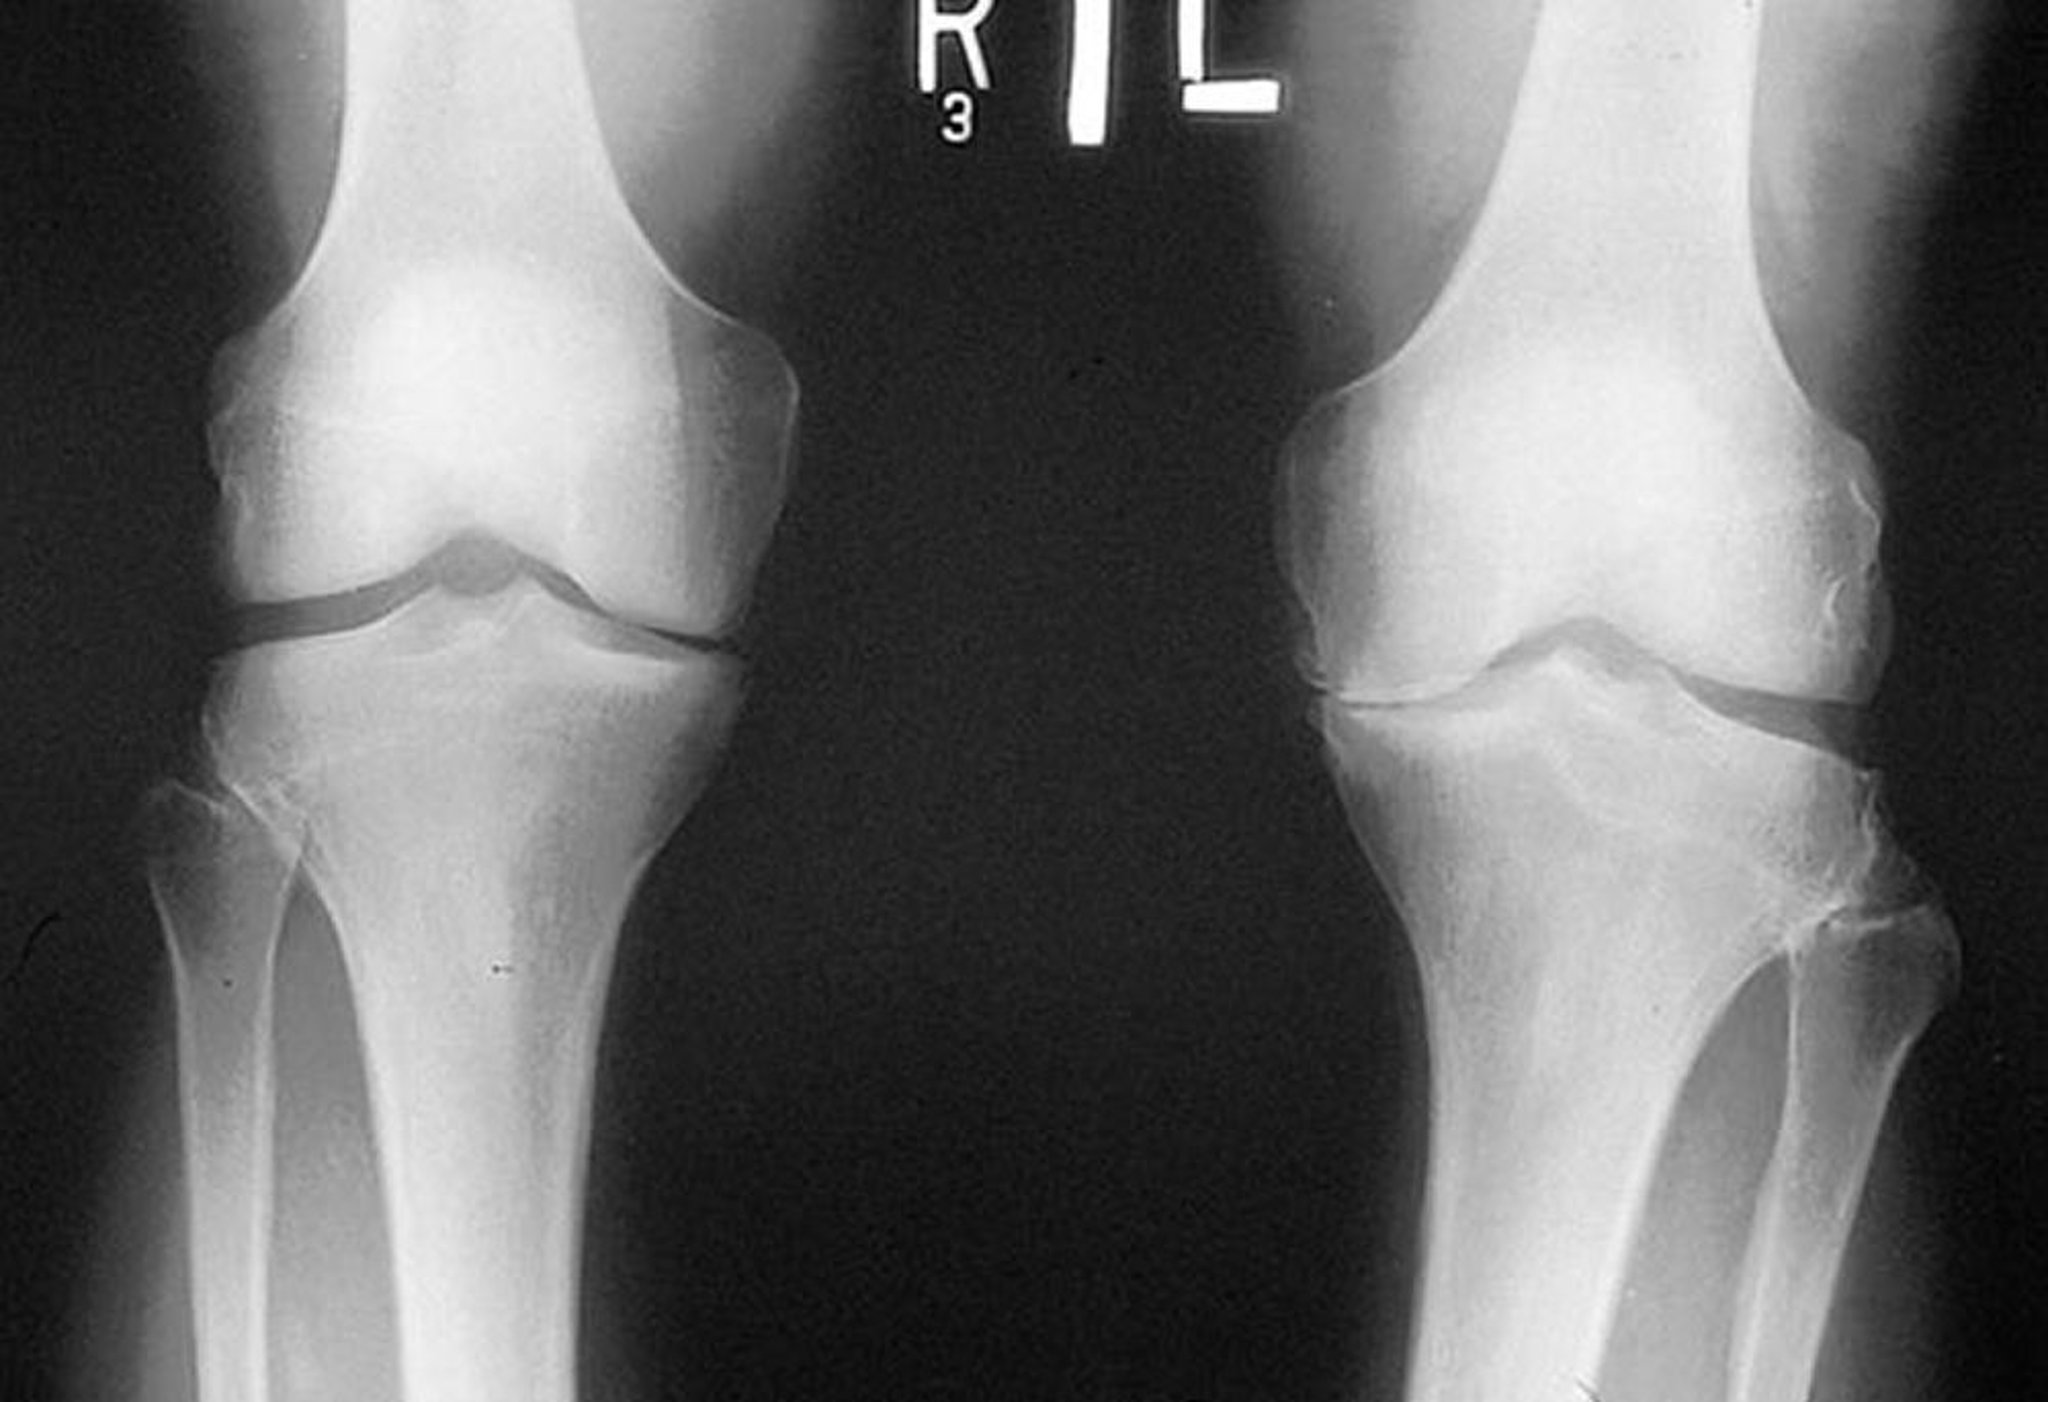

Radiografía de rodilla en la artrosis

Esta radiografía, tomada mientras el paciente está de pie, muestra que el espacio de la articulación tibiofemoral en el compartimento medial de ambas rodillas es estrecho, sobre todo a la izquierda. Los osteofitos marginales son visibles. Hay atrición de la meseta tibial medial izquierda.

By permission of the publisher. From Myers S: Atlas of Rheumatology. Edited by G Hunder. Philadelphia, Current Medicine, 2005.